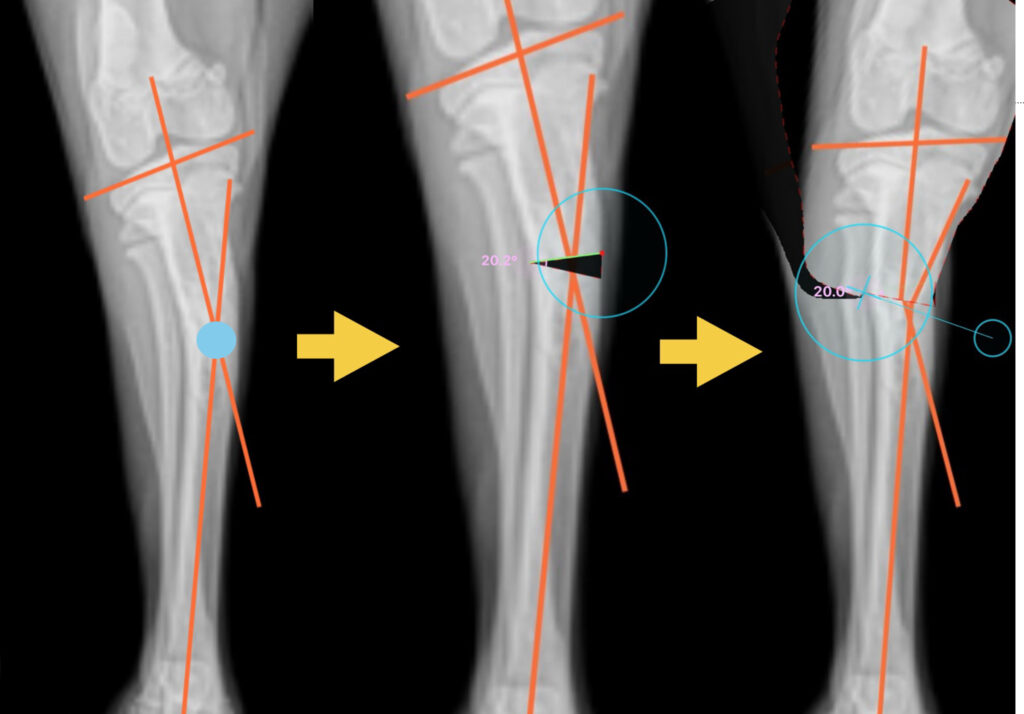

- まずは左側の写真で、骨の変形程度を算出するために、骨の長軸の交点(水色のマル)を求めます。

- 中央の写真では、交点が形成する角度から骨切り幅を算出し楔形に切り抜く幅を決定します。

- 右の写真で、骨切りした後に再び骨を接合し、変形が矯正されることを確認します。